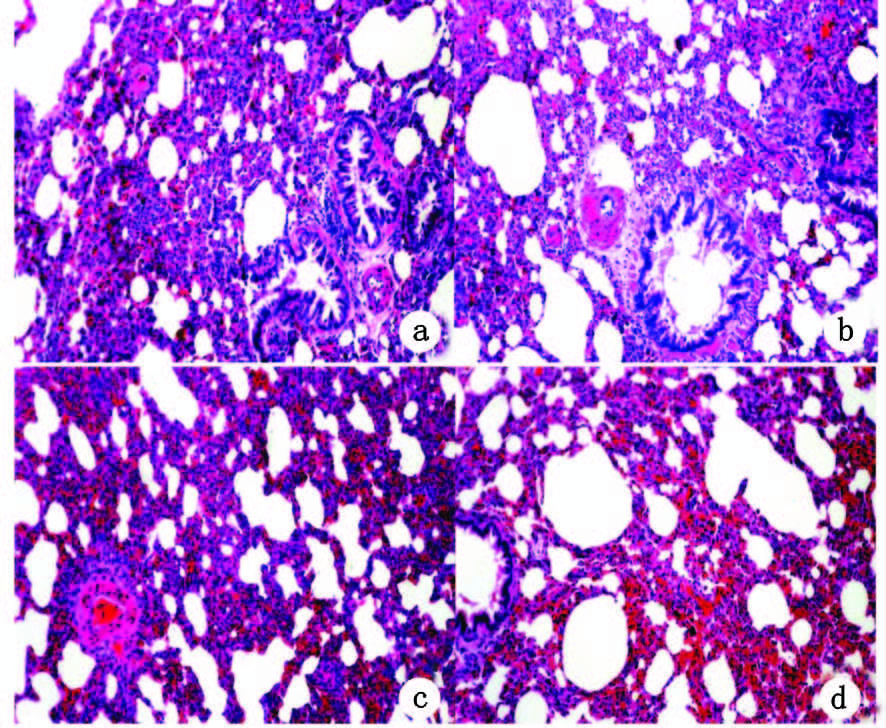

2 结果 2.1 病理学变化及肺损伤病理学评分电子显微镜下可以发现干热组肺泡间隔明显增宽,肺泡腔狭窄,支气管壁及部分肺泡间隔中可见大量炎症细胞渗出 ,肺泡壁血管明显充血、渗出性出血,支气管存在散在出血,常温组各时间点病理变化较干热组轻,见图 1。两组肺损伤评分总体比较差异具有统计学意义(t=3.279,P<0.05),干热组组内单因素方差分析差异具有统计学意义(F=12.32,P<0.01),常温组各组间单因素方差差异具有统计学意义(F=9.26,P<0.01),常温组与干热组肺损伤评分在休克后各时间点均高于对照组,干热组最大值(6.63±0.14)出现在1.5 h时,常温组最大值(5.50±0.20)在2.0 h时出现。见图 2。

| A、B:常温组2 h肺脏病理;C、D:干热组1.5 h时肺脏病理 图 1 2组大鼠不同时间点肺脏病理切片HE染色(×400) Fig. 1 Lung pathological section HE staining in two groups ( ×400) |